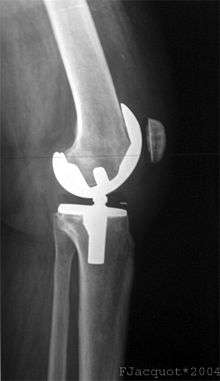

Partial knee replacement

Unicompartmental arthroplasty (UKA), also called partial knee replacement, is an option for some patients. The knee is generally divided into three "compartments": medial (the inside part of the knee), lateral (the outside), and patellofemoral (the joint between the kneecap and the thighbone). Most patients with arthritis severe enough to consider knee replacement have significant wear in two or more of the above compartments and are best treated with total knee replacement.[25] A minority of patients (the exact percentage is hotly debated but is probably between 10 and 30 percent) have wear confined primarily to one compartment, usually the medial, and may be candidates for unicompartmental knee replacement. Advantages of UKA compared to TKA include smaller incision, easier post-op rehabilitation, better post-operative range of motion, shorter hospital stay, less blood loss, lower risk of infection, stiffness, and blood clots, but a harder revision if necessary. While most recent data suggests that UKA in properly selected patients has survival rates comparable to TKA, most surgeons believe that TKA is the more reliable long term procedure. Persons with infectious or inflammatory arthritis (Rheumatoid, Lupus, Psoriatic ), or marked deformity are not candidates for this procedure.